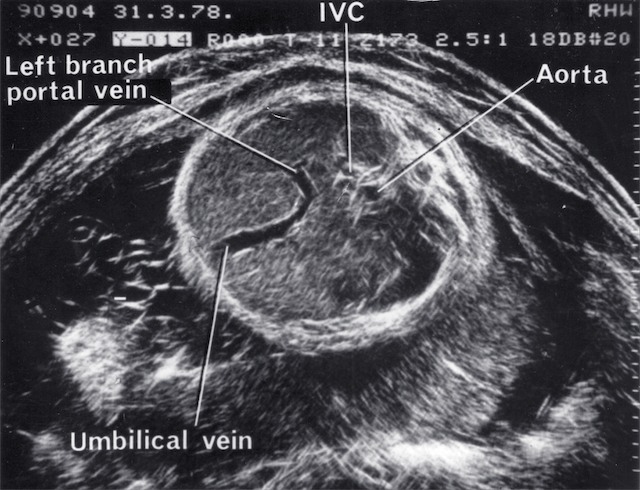

| 1968 | Demonstration of fetal orbits, heart, bladder, kidneys and scrotum |

| 1970 | Introduction of grey scale ultrasound, improving dramatically the demonstration of normal and abnormal structures in the fetus, placenta and mother |

| 1980 | Monitoring of fetal umbilical venous blood flow in normal and complicated pregnancies |

| 1980 | Demonstration of fetal lung, liver and bowel maturation by grey scale ultrasound |

- Fetal Doppler

- First umbilical vein flow measurement (1977)